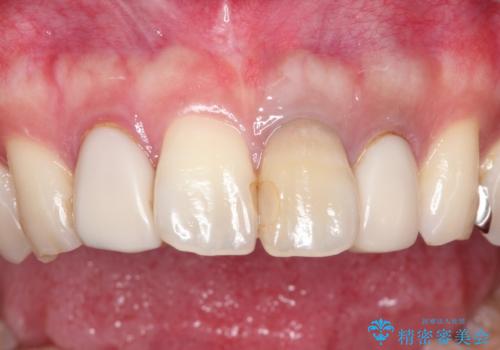

- 全体的なガタガタと前歯をきれいにしたいとのことで来院されました。

下の歯は重度のガタガタがあり、上の前歯は何本かが神経の治療がしてある状態でした。

インビザラインにて歯並びを整え、上顎の前歯にセラミックを装着する計画としました。